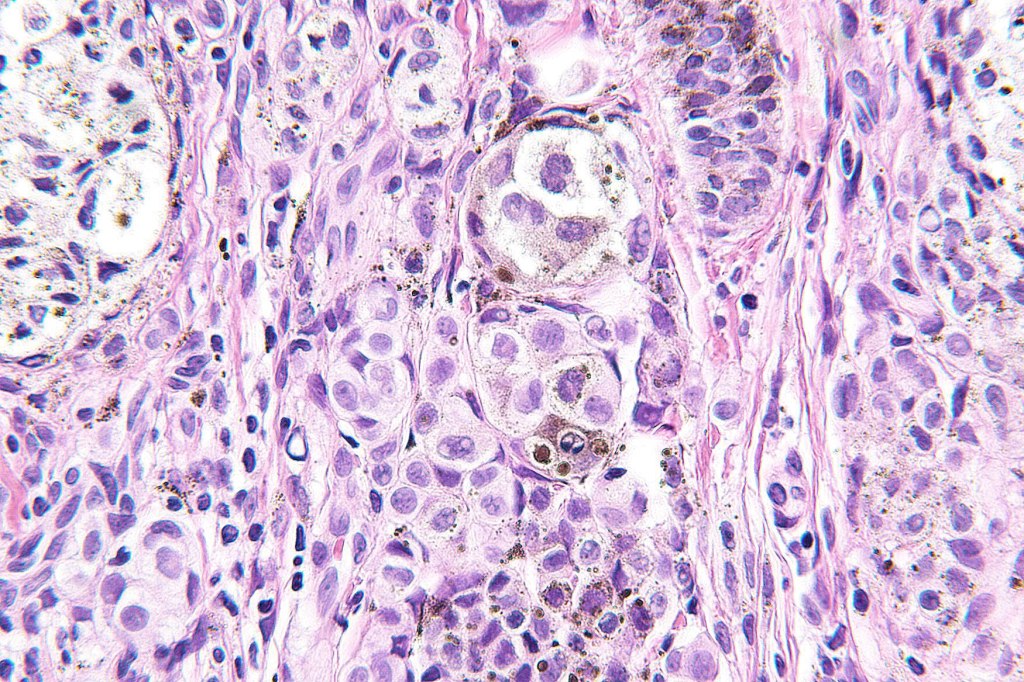

•May affect the tumor in part or whole

•Enlarged cells with copious eosinophilic, foamy or clear cytoplasm (some authors include melanoma with clear cell change in the same category)

•Variable pigmentation

•Nuclei vesicular or hyperchromatic

•Pleomorphism is not generally marked and indeed can be very subtle

•Variable mitotic activity

•DPAS granules

•Thought to be a result of abnormal or degenerative melanosome change